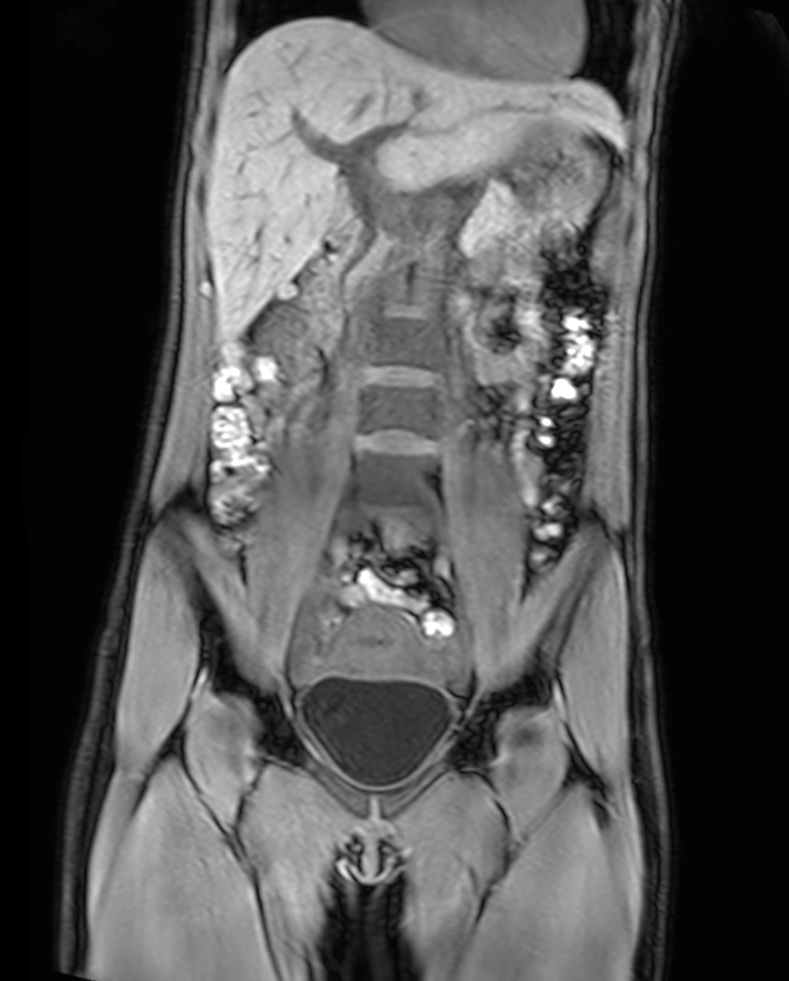

Coronal T2w TSE